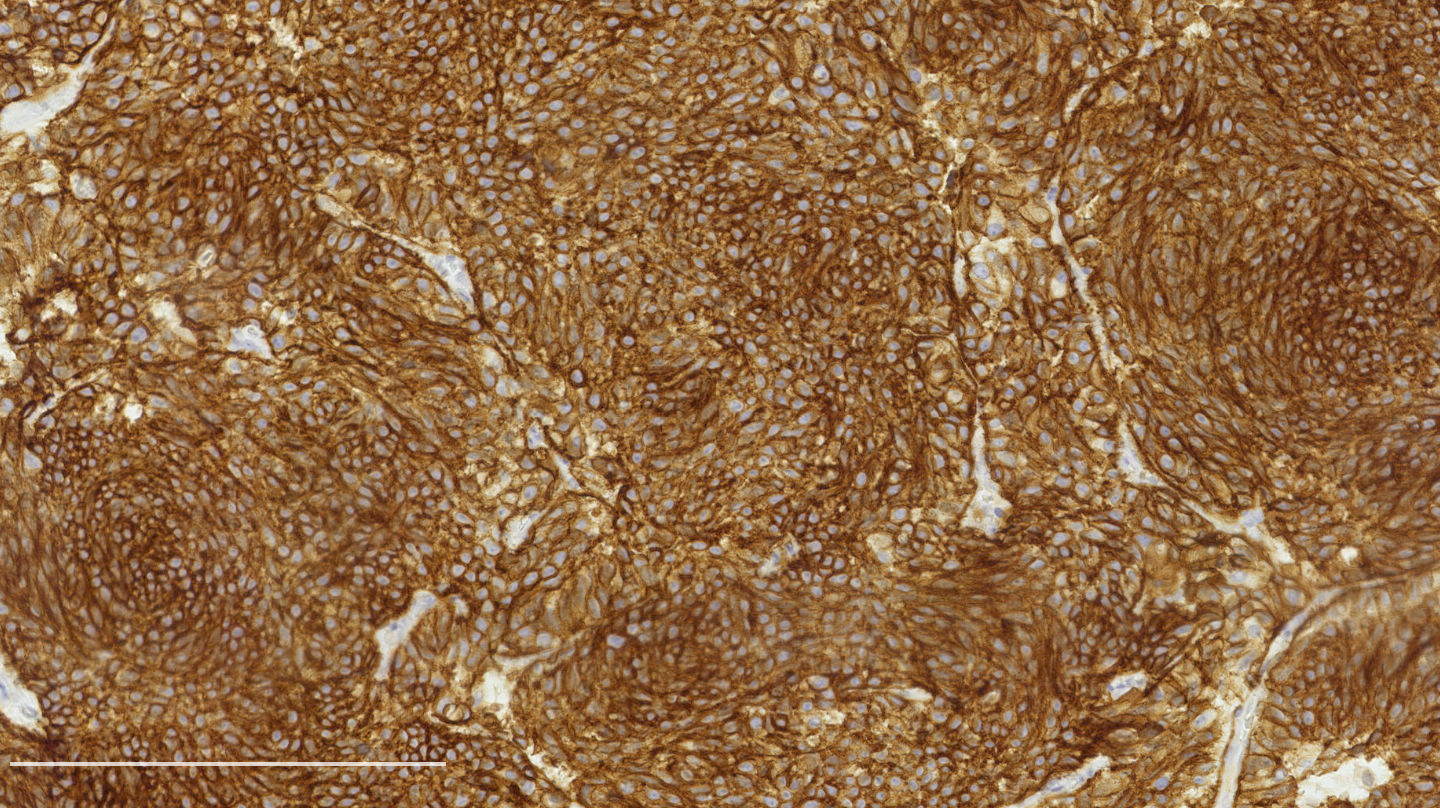

Contributed by Philippe Joubert, M.D., Ph.D.

Positive stains

- Chromogranin, synaptophysin, CD56: diffusely and strongly positive; can be negative in a small number of atypical carcinoids (Hum Pathol 2000;31:1255)

- Pancytokeratins: positive but up to 20% can be negative